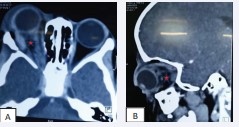

Figure 6: Parenchymal CT scan of the brain with contrast injection in axial section (A) and sagittal section (B) on D1 post-op, showing an empty tumour bed indicated by the red star.